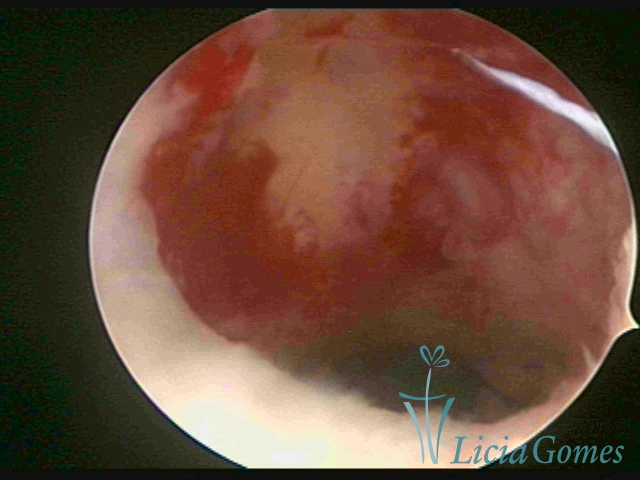

Retraction of a cesarean section scar, recess with a further bulge in the isthmic region

×

Retraction of a cesarean section scar